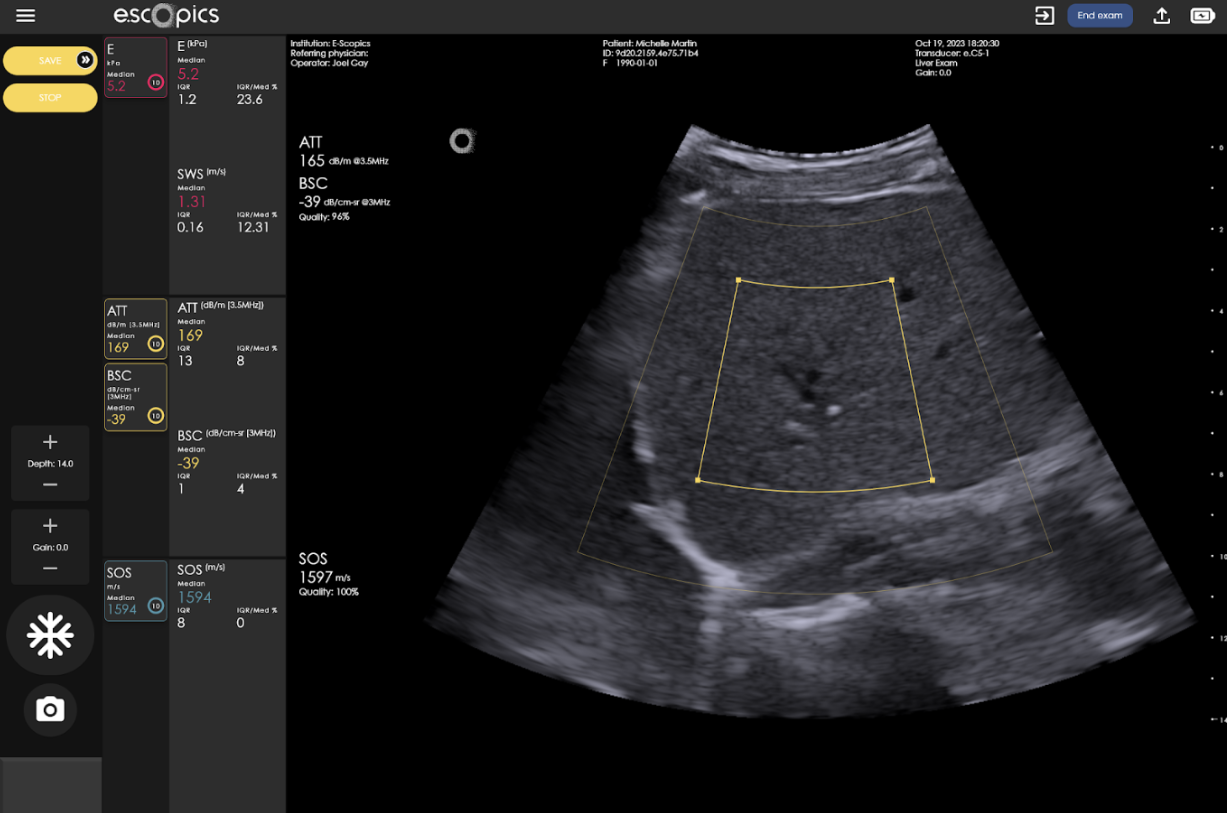

Increased intracellular fat elevates the backscattering coefficient (BSC), making the liver appear brighter (“bright liver”). Fat also causes higher attenuation (ATT), i.e. signal loss and posterior shadowing, and decreases the speed of sound (SOS) as lipid (fat) medium is a slower medium than healthy (aqueous) liver tissues.

Hepatoscope, thanks to its QUS workflow, is the unique system offering real-time ATT, BSC and SOS estimation based on ultrafast ultrasound imaging. The estimation of BSC and ATT are performed using a reference-based method. This approach is powerful because it uses a well-characterized reference phantom to cancel out system-dependent variables.

By comparing signals from the tissue to the signal from the phantom, one can isolate the intrinsic acoustic properties of the tissue. Coupling ultrafast ultrasound imaging with the reference-based approach presents several benefits, including improved accuracy and robustness thanks to extensive signal averaging and compounding, mitigation of motion artifacts by “freezing” physiological movement, better statistical averaging for heterogeneous tissues, larger sampling volume in the liver, and reduced operator dependency, leading to more consistent and reliable quantitative assessments, which is crucial for monitoring fat content in the liver of patients with MASLD.

Regarding SOS estimation, Hepatoscope implements a patented method developed at E-Scopics (Heriard-Dubreuil et al. 2023). The core innovation is a novel SOS estimation technique that utilizes an angular approach based on plane waves to exploit refraction properties in layered media. This allows for the inference of local speed of sound values directly from angular raw data, offering robust, accurate, and real-time measurements with significantly fewer emissions and lower computational time compared to the current other existing methods.

Ultrafast acquisitions enable a real-time measurement of a quality index, guiding operators by quantifying acoustic signal reliability. This multifactorial index, derived from signal stability, signal-to-noise ratio, and model goodness-of-fit, indicates trustworthy measurements when high.

Clinical benefits include increased confidence and reduced error by discarding unreliable data (e.g., from rib shadows, poor probe contact, large blood vessels). Immediate visual feedback with B-mode imaging optimizes probe positioning and data acquisition, dramatically improving measurement reproducibility and reliability.